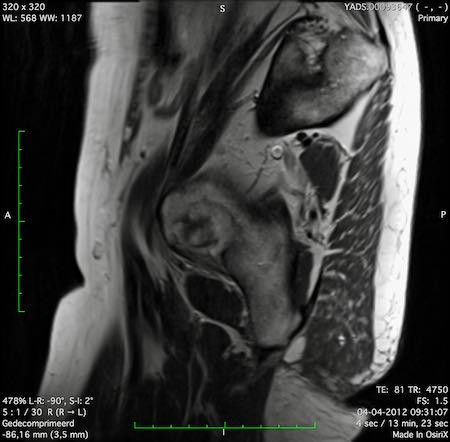

Đặc điểm MRI

- Thường khó xác định

- Thường biểu hiện nhưdày thành ruột lan tỏa, đoạn dài

- Kiểu tăng trưởng dưới niêm mạc, cho ra mộtHình ảnh “bia” (target)trên các hình ảnh cắt ngang

- Thâm nhiễm mỡ trực tràng lan tỏalà phổ biến

Hình ảnh

Các hình ảnh được cung cấp cho thấy ung thư biểu mô tế bào nhẫn với tình trạng dày lan tỏa thành trực tràng, hình ảnh bia bắn điển hình, và sự xâm lấn mỡ mạc treo trực tràng.